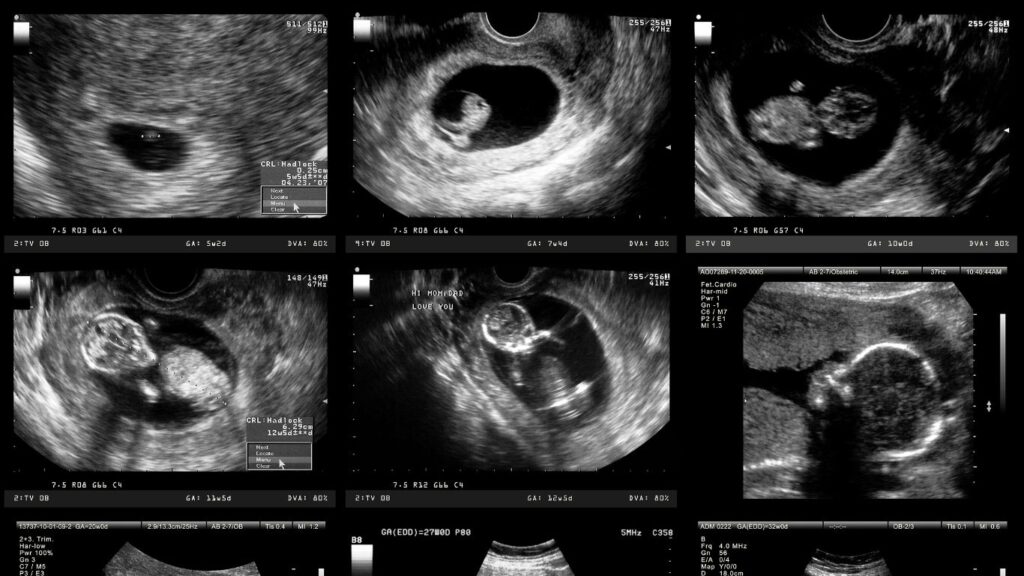

Ecografías Obstétricas: Cuidado y Precisión en Querétaro

En Altaria, nos dedicamos a proporcionar una atención excepcional en ecografías obstétricas, centrada en el bienestar de la madre y el bebé. Nuestro equipo cuenta con una sólida formación en medicina materno-fetal, lo que nos permite ofrecer un seguimiento detallado durante el embarazo. Utilizamos tecnología de última generación en nuestro centro de ecografías, garantizando precisión […]

Ultrasonidos Estructurales: Diagnóstico en Querétaro

En Querétaro, los ultrasonidos estructurales se han convertido en una herramienta esencial para el diagnóstico prenatal. En Altaria, nos destacamos por ofrecer servicios de alta calidad en este ámbito, garantizando un análisis exhaustivo del desarrollo fetal. Este método permite detectar posibles anomalías desde etapas tempranas, brindando tranquilidad a los futuros padres y asegurando un seguimiento […]